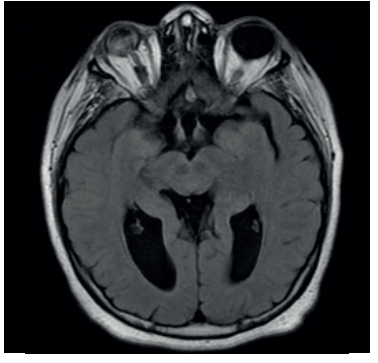

Paciente de sexo femenino, 37 años, derivada desde la policlínica de fertilidad. A los 11 años, en el contexto de evaluación por talla baja (debajo de 2 desvíos estándar (DE) de la media para edad y sexo), con hipocrecimiento (velocidad de crecimiento menor a -1 DE por más de un año, acompañado de talla baja) y retraso del desarrollo puberal, se diagnosticó hipogonadismo hipogonadotrófico y déficit de GH. Como etiología, presenta síndrome de De Morsier diagnosticado por resonancia nuclear magnética (RNM) a la misma edad que evidenció ausencia de septum pellucidum, hipoplasia del nervio óptico con hipoplasia de cuerpo calloso, tallo hipofisario y quiasma óptico traccionados ocupando la silla turca. Además, no se reconoce la neurohipófisis (figuras 1,2 y3).

La clínica es muy variada. Pueden ocurrir alteraciones visuales, neurológicas y endócrinas. Las alteraciones visuales ocurren secundariamente a la hipoplasia del nervio óptico, que van desde un daño parcial en la visión hasta ceguera, también se asocia a estrabismo y nistagmo. Esta paciente presentó desprendimiento de retina congénito en ojo derecho y nistagmo ocular bilateral. Las secuelas neurológicas comprenden retraso en el desarrollo cognitivo, convulsiones, hasta incluso parálisis cerebral. Cuando se tiene al menos una sospecha de SOD, que en esta paciente se evidenció por el fenotipo al nacimiento, labio leporino, trastorno ocular y nistagmo, se debe solicitar una RNM para evaluar anormalidades del hipotálamo-hipófisis y posibles defectos de la línea media5. Para el diagnóstico, deben estar presentes dos de tres criterios: ausencia del septum pellucidum, disgenesia del cuerpo calloso e hipoplasia del nervio óptico. Otros hallazgos posibles son microftalmia o anoftalmia, coloboma, hipófisis ectópica o hipoplasia, tallo hipofisario hipoplásico7. Los ejes hipofisarios más frecuentemente afectados son el somatotropo, corticotropo, tirotropo y déficit de hormona antidiurética (ADH). Esta paciente se presentó con un déficit de GH y un hipogonadismo hipogonadotrófico. En un estudio realizado en Estados Unidos, en 1984, observaron que de una muestra de 16 pacientes con SOD en un seguimiento de 3,5 años. El orden y grado de afectación de los ejes hormonales era similar a lo reportado en la literatura hasta el momento. Encontraron que 73% presentaba déficit GH aislada, y 34% de deficiencia de ACTH. Le siguen el déficit de hormona tirotropa (TSH) y ADH en 24% y 21%, respectivamente8. Se concluye que los déficits hormonales son frecuentes y pueden progresar en el tiempo, por lo que la evaluación endocrinológica regular es necesaria para la correcta sustitución y prevención de comorbilidades asociadas al hipopituitarismo.